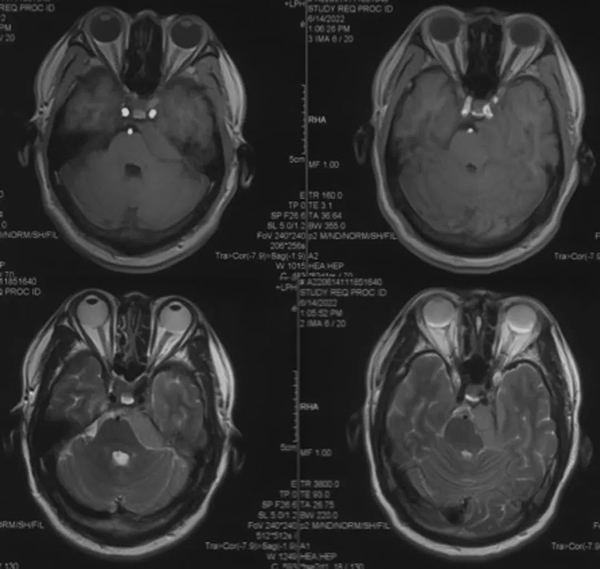

头颅MRI

T1、T2像显示左侧岩斜区肿瘤,骑跨中后颅窝,呈等T1和长T2信号,肿瘤呈实性,边界清楚,不伴瘤周水肿。

头颅MRI增强

增强轴位和冠状位显示肿瘤均匀强化,肿瘤基底主要位于左侧中上斜坡及岩骨背侧,向前达鞍区颈内动脉后方,向内侧达椎动脉,向外侧超过内听道水平,向下达内听道水平。